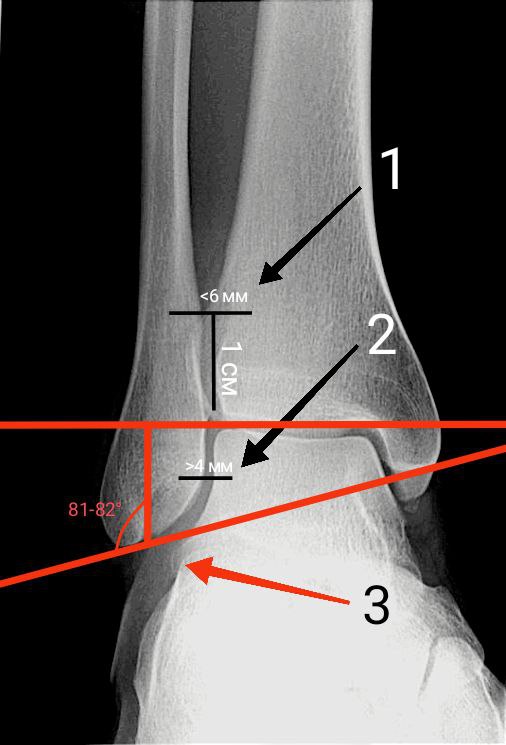

ancl rg1